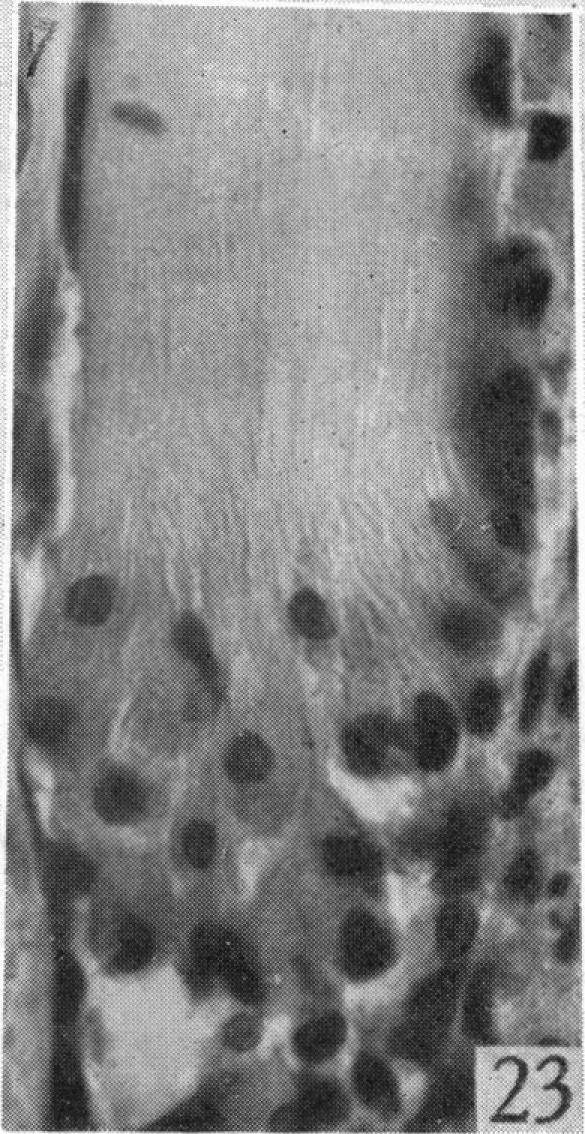

An experimental study of the regeneration of mammalian striped muscle.

摘要